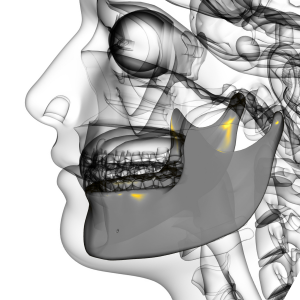

Our practice uses advanced 3D imaging, facial scanning, and digital surgical planning to design a custom guide for your implant placement. This technology ensures every implant is positioned with micron-level accuracy, leading to a perfect fit and faster healing.

With thousands of implants placed, our skilled surgical team combines digital precision with human expertise—delivering results that look, feel, and function naturally. Our fully digital process is faster, more flexible, and entirely customized to you.

Experience the future of implant dentistry—digitally designed, expertly placed, beautifully perfected.